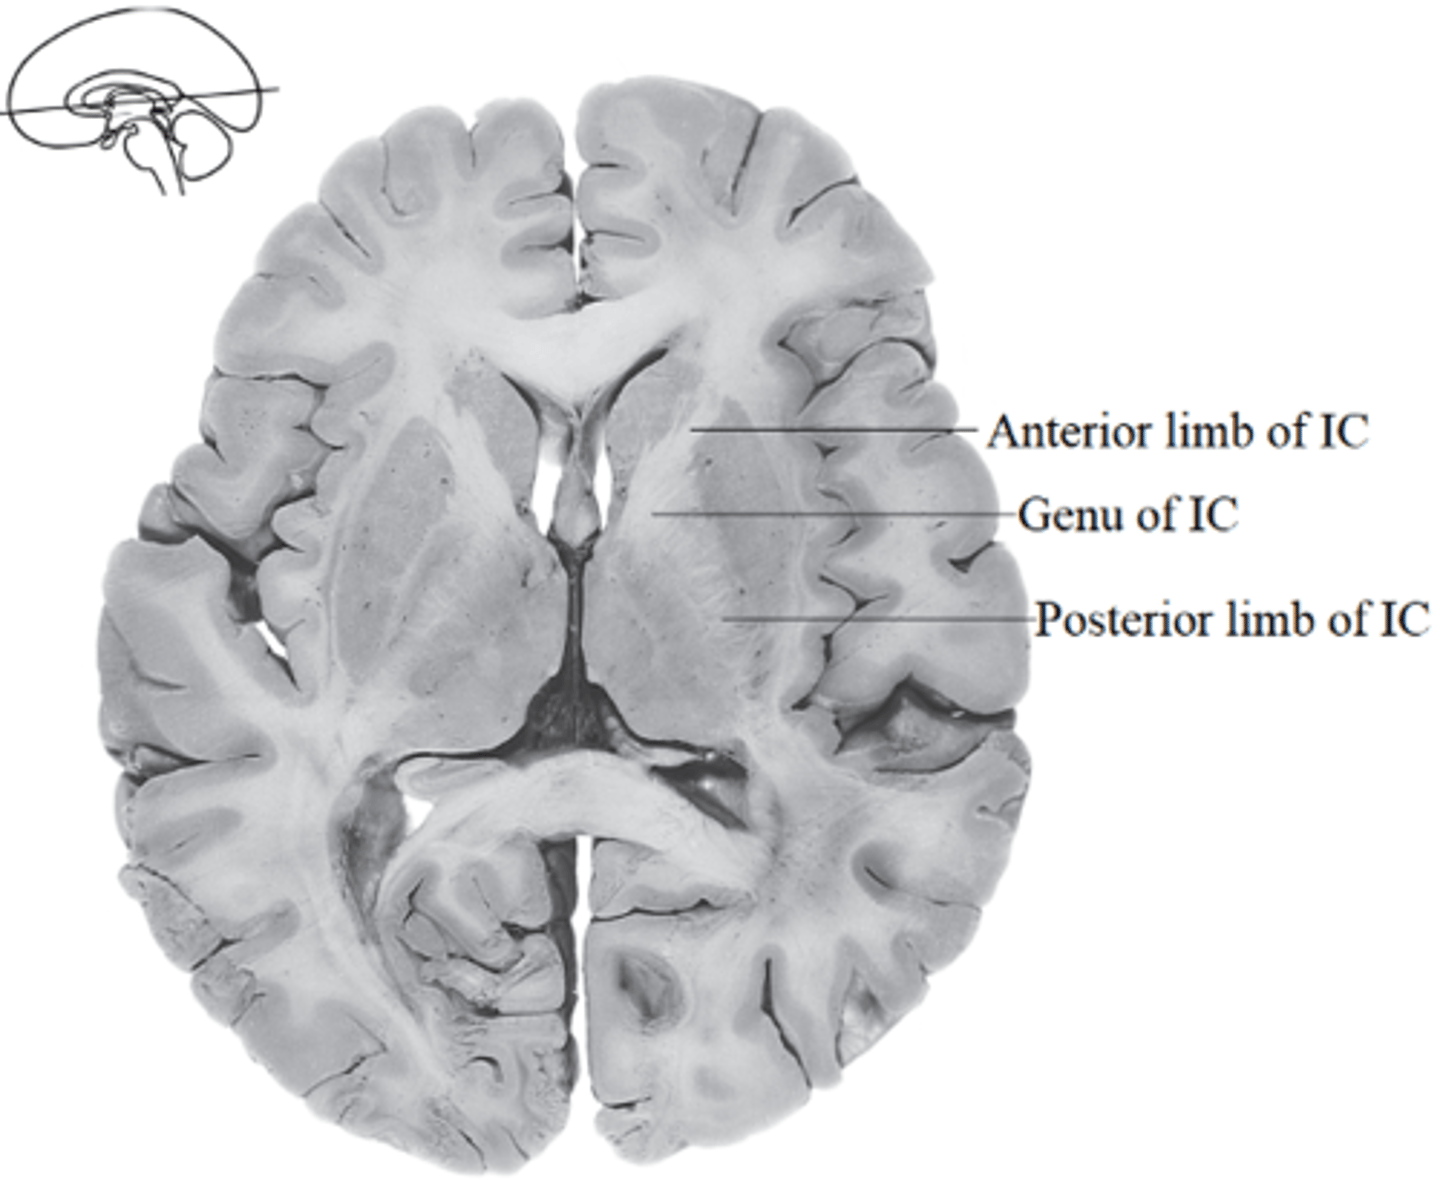

what cerebral white matter structure is a tract that carries sensory and motor information to and from the cerebral cortex?

internal capsule

what cerebral white matter structure is found between the basal ganglia?

internal capsule

what are the 3 regions of the internal capsule?

1. anterior limb

2. genu

3. posterior limb